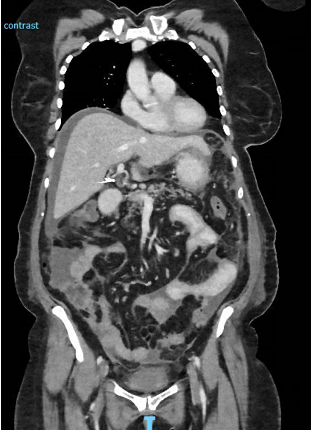

In hospital the patient was extensively investigated for a unifying diagnosis to account for her presentation. Cardiac, hepatic, and renal failure as causes for ascites were ruled out through normal biochemistry (including brain natriuretic peptide level), and imaging including an abdominal ultrasound confirming a normal liver contour and no secondary signs of chronic liver disease or portal hypertension. Of initial interest, the tumour marker cancer antigen 125 was elevated at 476units/mL (normal range <35), however a pelvic ultrasound was normal, with gynaecology opinion outlining that an ovarian malignancy as the underlying cause for presentation was unlikely. For completeness, a sexually transmitted infection screen was inconsistent with pelvic inflammatory disease. Given no diagnosis had been made, two separate paracentesis procedures to capture fluid for analysis were performed. The serum-ascites albumin gradient on both was <1.1g/L suggesting an exudative pathology such as infection or malignancy. Despite this, multiple fluid cultures, including assessment for tuberculosis, and both cytological assessments were normal. A repeat CT, now including the chest, again demonstrated only ascites with no evidence of infection, lymphadenopathy or malignancy in either the abdominal or thoracic cavities (Figure 2).

Figure 2 Coronal slice of repeat CT chest/abdomen/pelvis with ongoing ascites and peritoneal stranding, however no other signs of infection or malignancy.